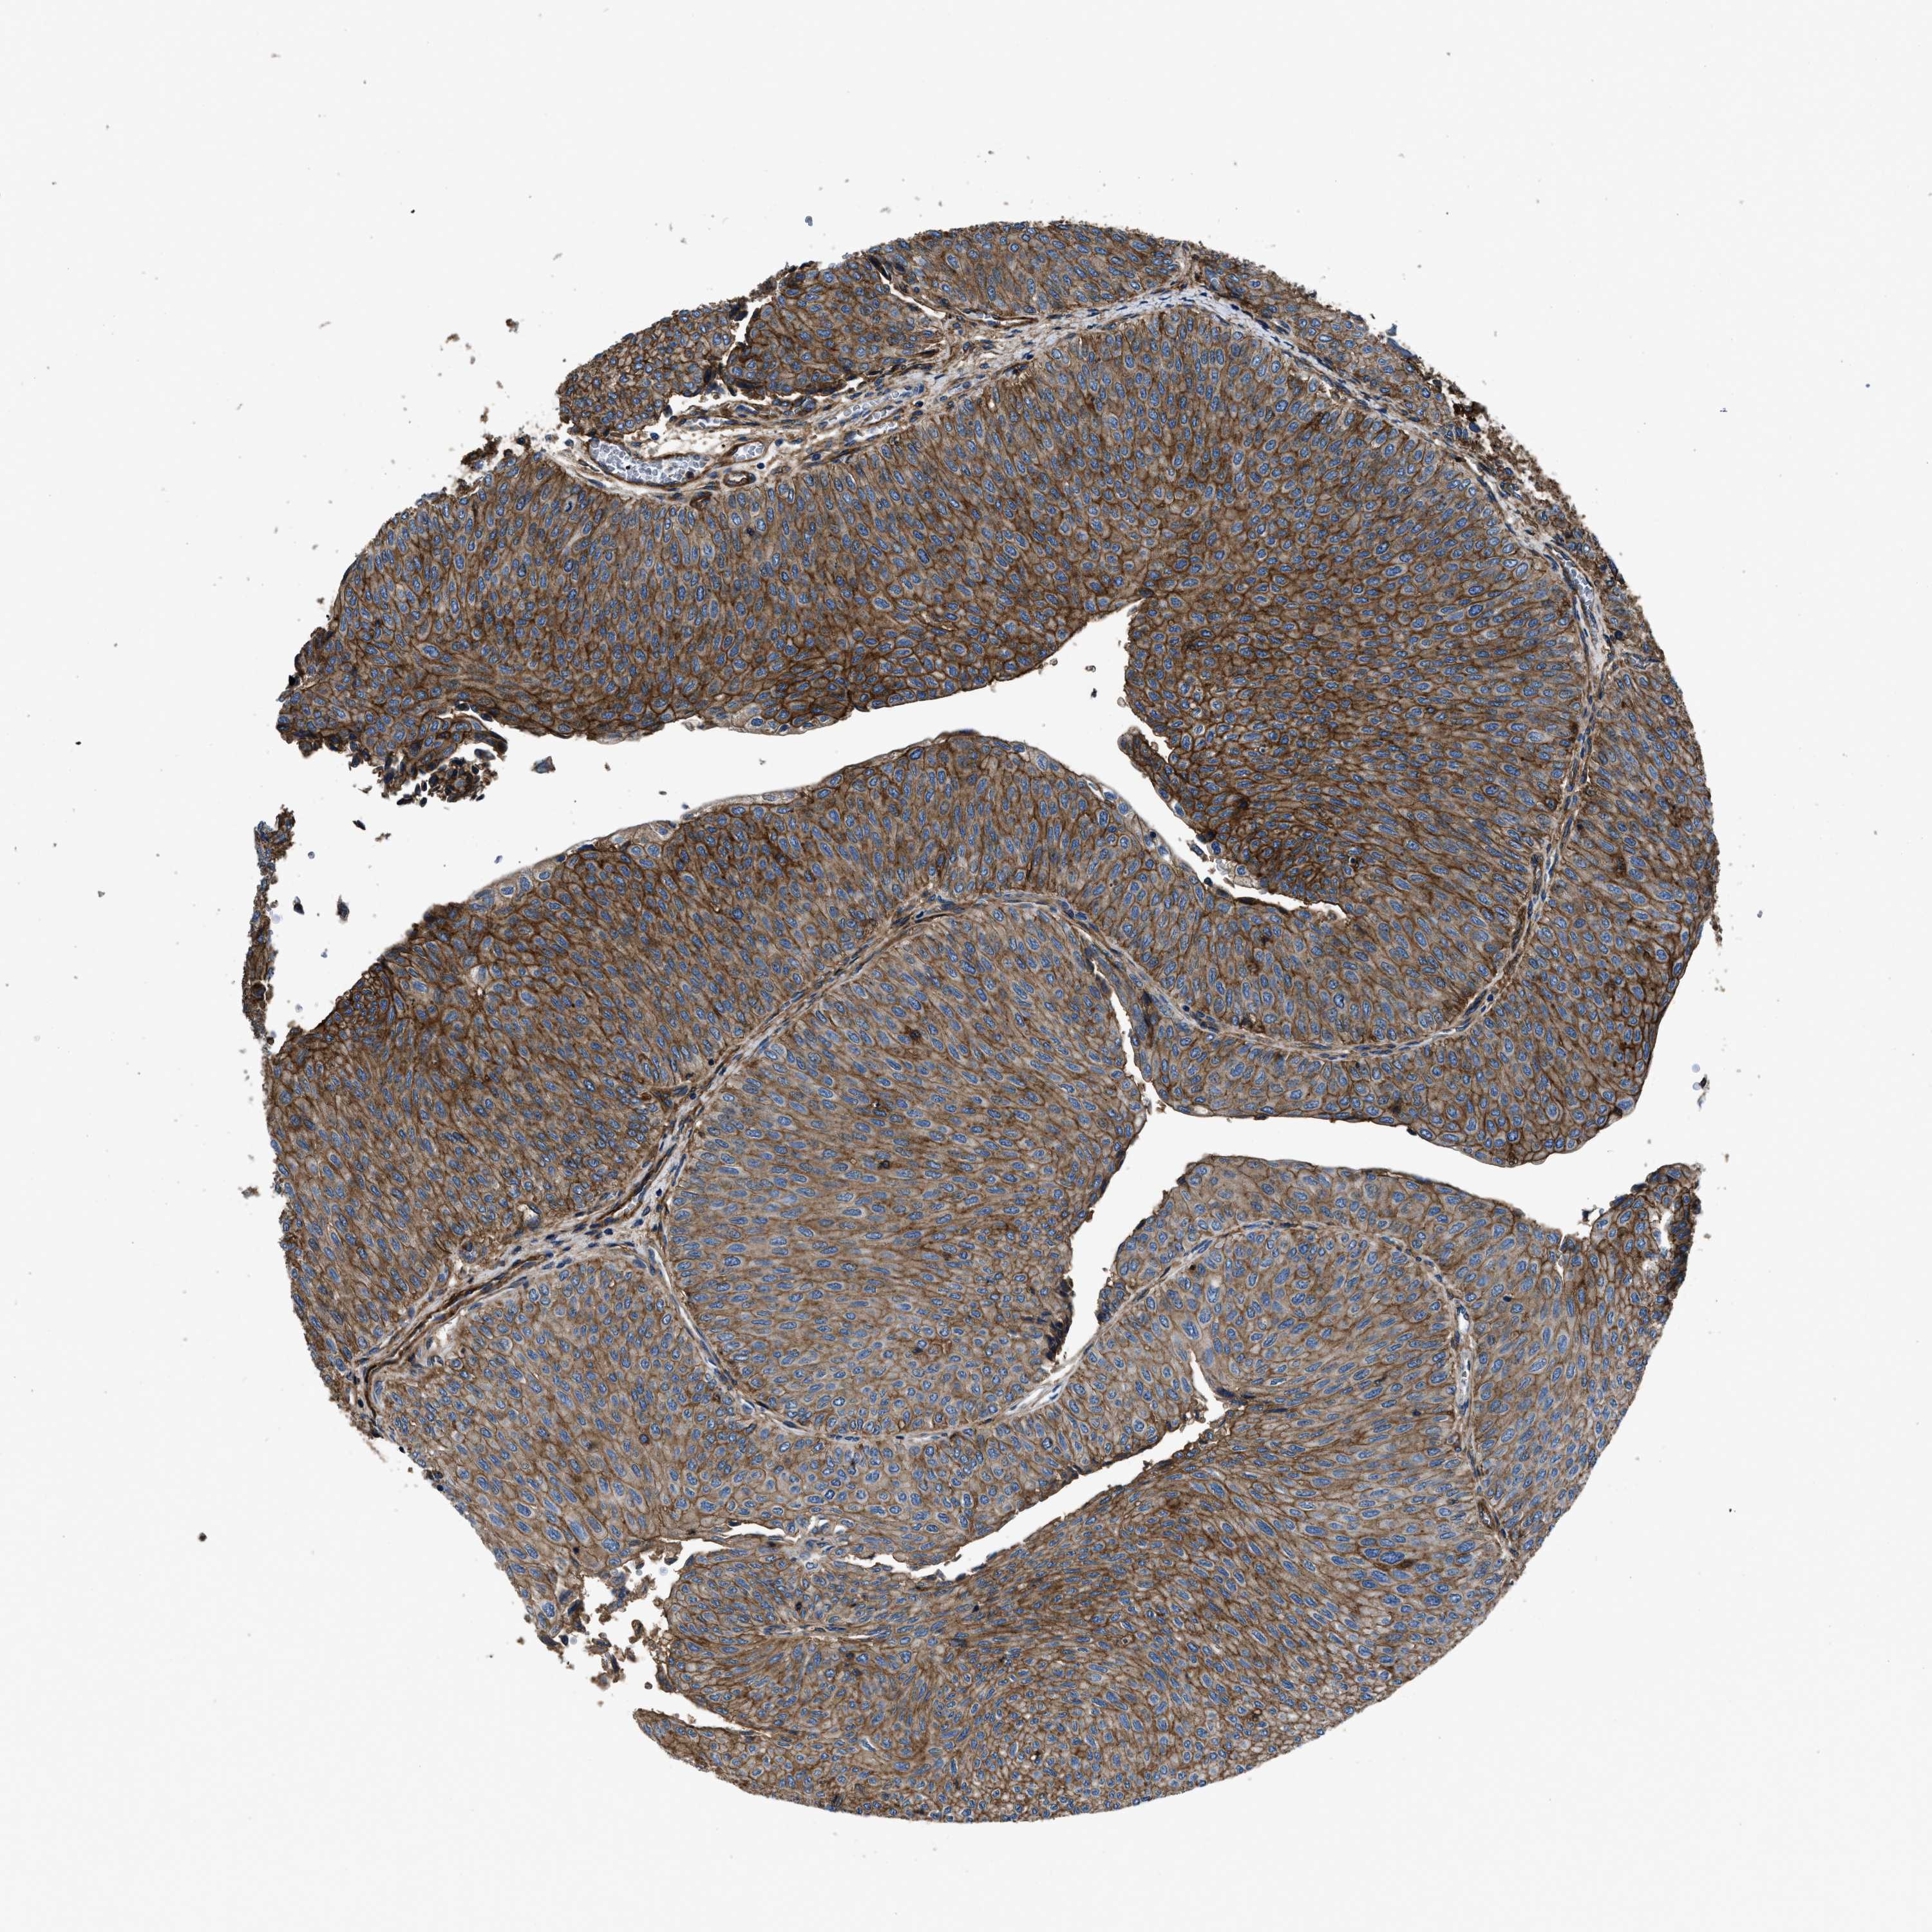

UROTHELIAL CANCER - Protein expressioni

A mouse-over function shows sample information and annotation data. Click on an image to view it in a full screen mode. Samples can be filtered based on level of antibody staining by selecting one or several of the following categories: high, medium, low and not detected. The assay and annotation is described here.

Note that samples used for immunohistochemistry by the Human Protein Atlas do not correspond to samples in the TCGA dataset.

Antibody stainingi

Antibody staining in the annotated cell types in the current human tissue is reported as not detected, low, medium, or high, based on conventional immunohistochemistry profiling in selected tissues. This score is based on the combination of the staining intensity and fraction of stained cells.

Each image is clickable and will lead to virtual microscopy that enables deeper exploration of all samples and also displays staining intensity scores, fraction scores and subcellular localization as well as patient and tissue information for each sample.

Antibody HPA009285

Antibody HPA017139

Antibody CAB017826

Urothelial carcinoma, Low grade

Urothelial carcinoma, High grade